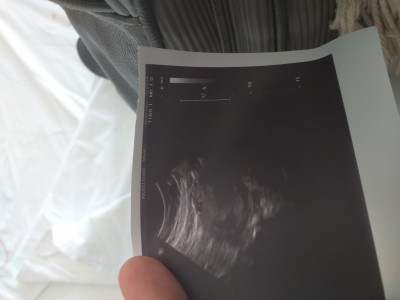

Cinsiyet tahmini 13+6

Sizce nedir

Kız bebek?

Doktor bişey dedi mi

Bacak arası ise bu gördüğüm fotoğrafta , boş görünüyor :)